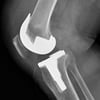

무릎 인공관절의 최신 수술법